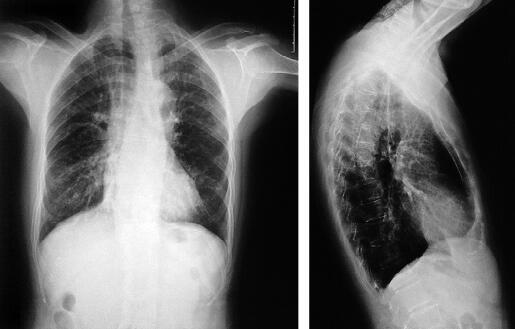

患者为电工,既往体健。吸烟40年,每天吸烟约10支。患者于1个月前无明确诱因出现咳嗽,夜间明显,无咳痰,偶感气短,但无喘息。未服用任何药物,症状逐渐加重。近2周自觉发热,未测体温。夜间偶有发冷和寒战,无盗汗。发病2周时胸部X线示右下肺透过度略下降(图1),口服“头孢”一周效果不佳。行血常规检查发现外周血白细胞计数增高,为15.7×109/L;嗜酸性粒细胞增高,计数达6.94×109/L,百分比为44.2%,静脉使用头孢类抗生素(具体药物及剂量不详),三天后复查外周血白细胞计数仍增高(17.6×109/L),嗜酸性粒细胞为8.98×109/L,百分比为51%。治疗一周症状无改善。为明确诊断及治疗来诊。

图1